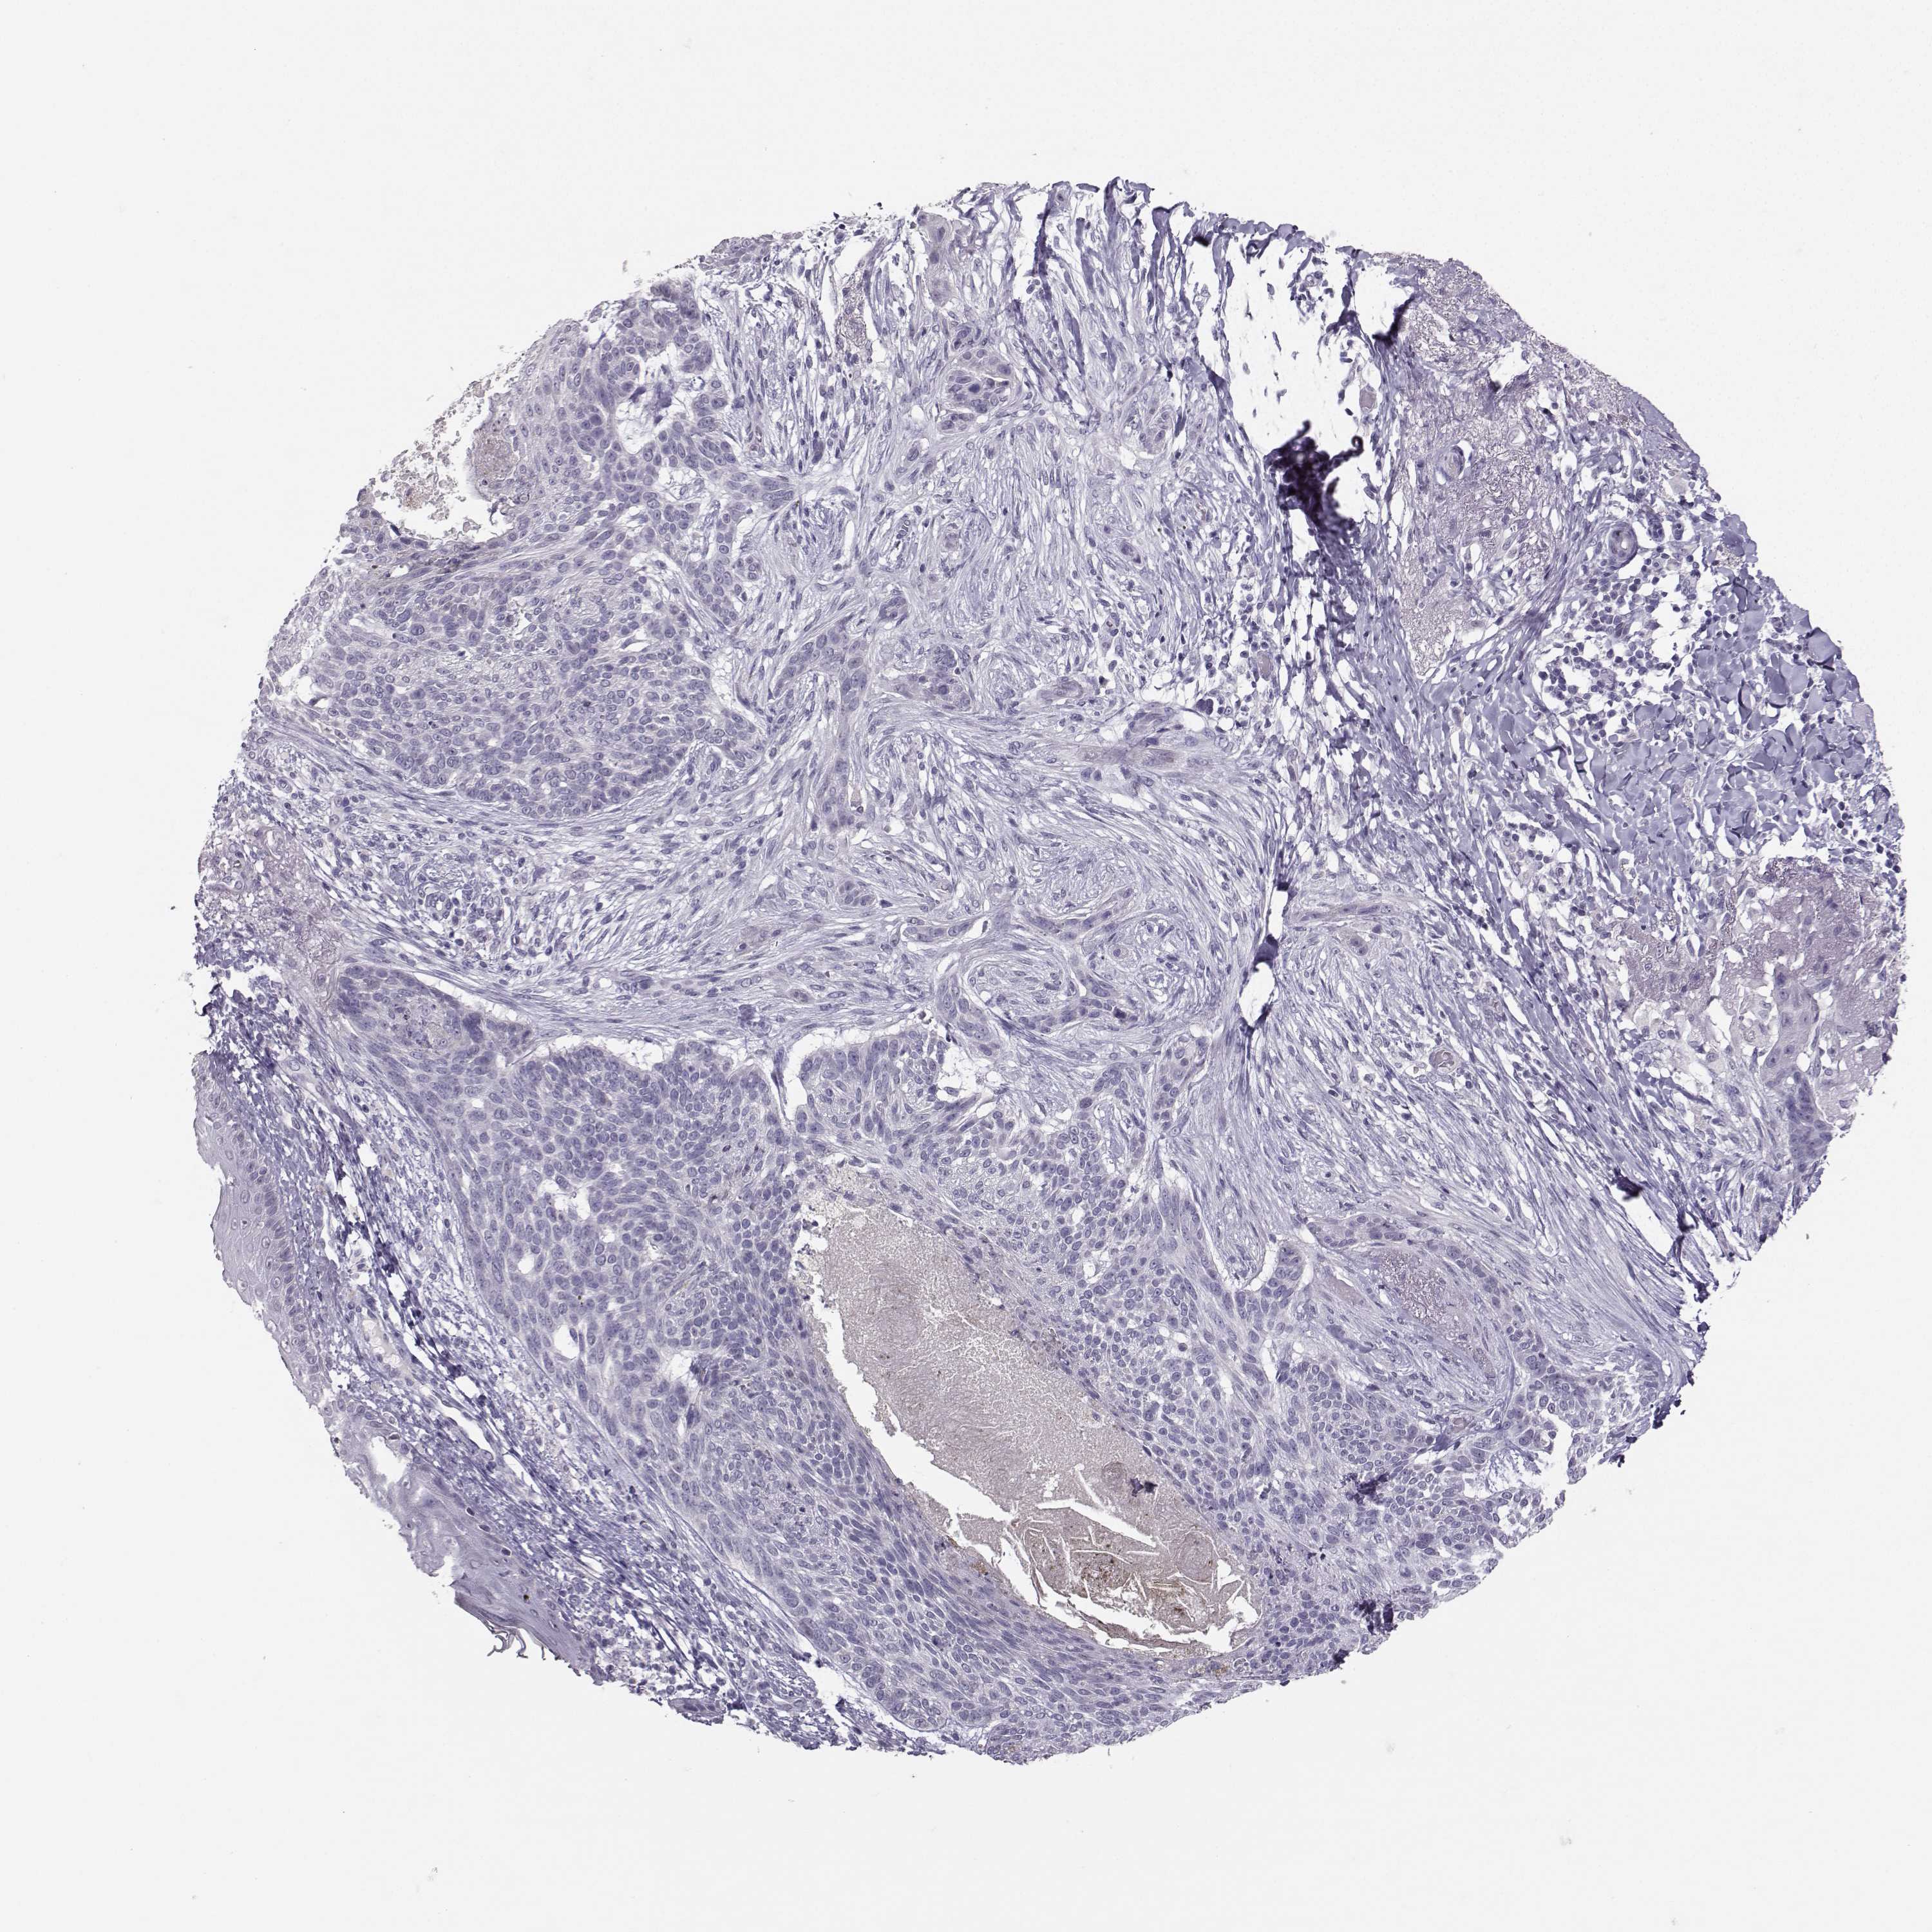

Basal cell and squamous cell cancer

SKIN CANCER - Protein expressioni

A mouse-over function shows sample information and annotation data. Click on an image to view it in a full screen mode. Samples can be filtered based on level of antibody staining by selecting one or several of the following categories: high, medium, low and not detected. The assay and annotation is described here.

Each image is clickable and will lead to virtual microscopy that enables deeper exploration of all samples and also displays staining intensity scores, fraction scores and subcellular localization as well as patient and tissue information for each sample.

Antibody HPA056908

Squamous cell carcinoma, NOS